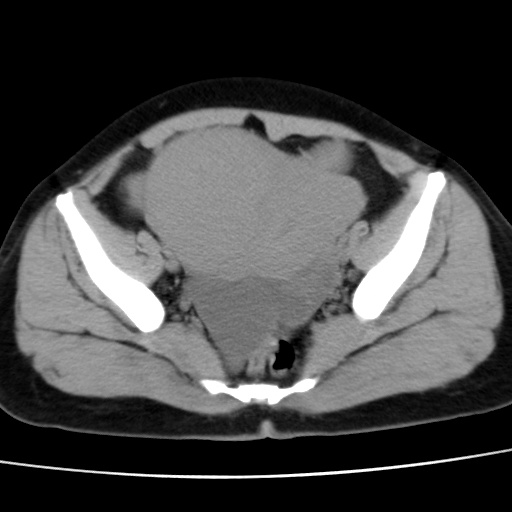

子宫多发肌瘤吗

多发性子宫肌瘤.

考虑多发子宫肌瘤,子宫直肠窝双囊性占位,另直肠周围脂肪密度增高,不知有何病史

支持考虑多发子宫肌瘤~!子宫直肠陷凹积液?

支持考虑多发子宫肌瘤~!子宫直肠陷凹积液!

子宫肌瘤,宫体部后方见液性密度影,是肠道还是子宫与直肠陷窝积液不好说,我觉得它的位置有点高

支持考虑多发子宫肌瘤!子宫直肠陷凹积液!

患者发热,而子宫直肠窝液性灶有明显边缘且局限且囊性,不除外为包裹性积液或脓肿

支持考虑多发子宫肌瘤,子宫直肠陷凹积液可能。

考虑多发子宫肌瘤

1)考虑子宫肌瘤可能性大。2)子宫后方囊性占位性病变,不排除卵巢囊肿可能。

考虑多发子宫肌瘤。子宫后方囊性占位性病变,不排除卵巢囊肿可能。